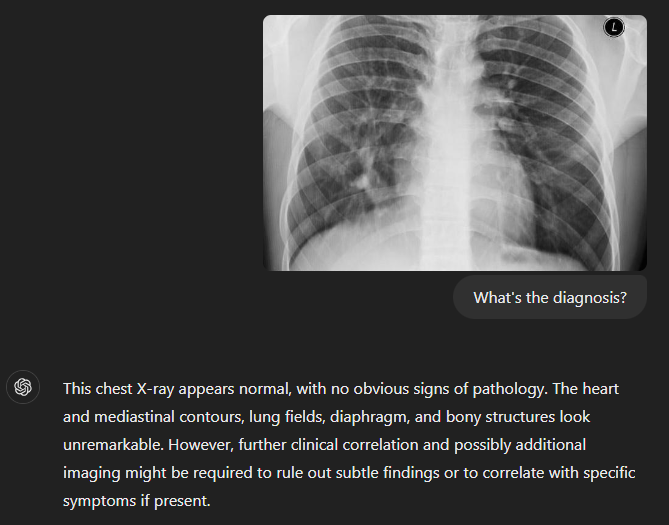

I would do anesthesia. Less vulnerable to AI. And before I get downvoted, put any CXR or CT into 4o and it will match the impression on the report most of the time. Now imagine how advanced it will be in 6 years when you can practice as an attending

I just put in one CXR from Radiopaedia, which is on the open internet and GPT could have been trained on, and it missed the diagnosis entirely.

GPT-4 is not ready for medical image analysis. https://pubs.rsna.org/doi/10.1148/radiol.242286

Case of scimitar syndrome. https://radiopaedia.org/cases/scimitar-syndrome-27 Using free chatgpt so 4o.